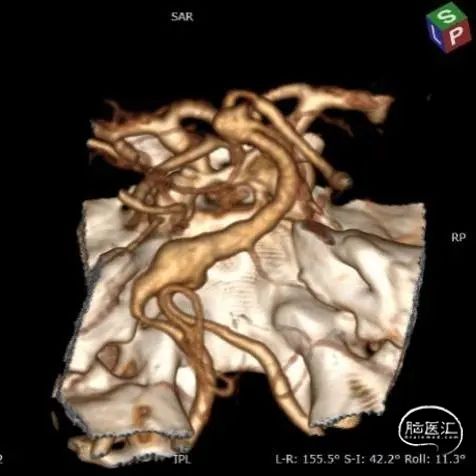

入院后立即行脑血管造影提示椎基底冗长扩张(基底动脉脑桥部分最宽处约5.2mm),伴有基底动脉多发动脉瘤,基底动脉尖动脉瘤(最大径约8mm)伴子囊和基底动脉下段动脉瘤(最大径约11mm)(图2)。